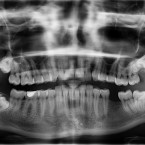

Zkažené zuby: Mohou vás i zabít

Samotná bolest zubů může být způsobena mnoha příčinami. Nejčastěji je na vině zubní kaz, tím ovšem problémy jenom začínají. Kaz...

Číst více